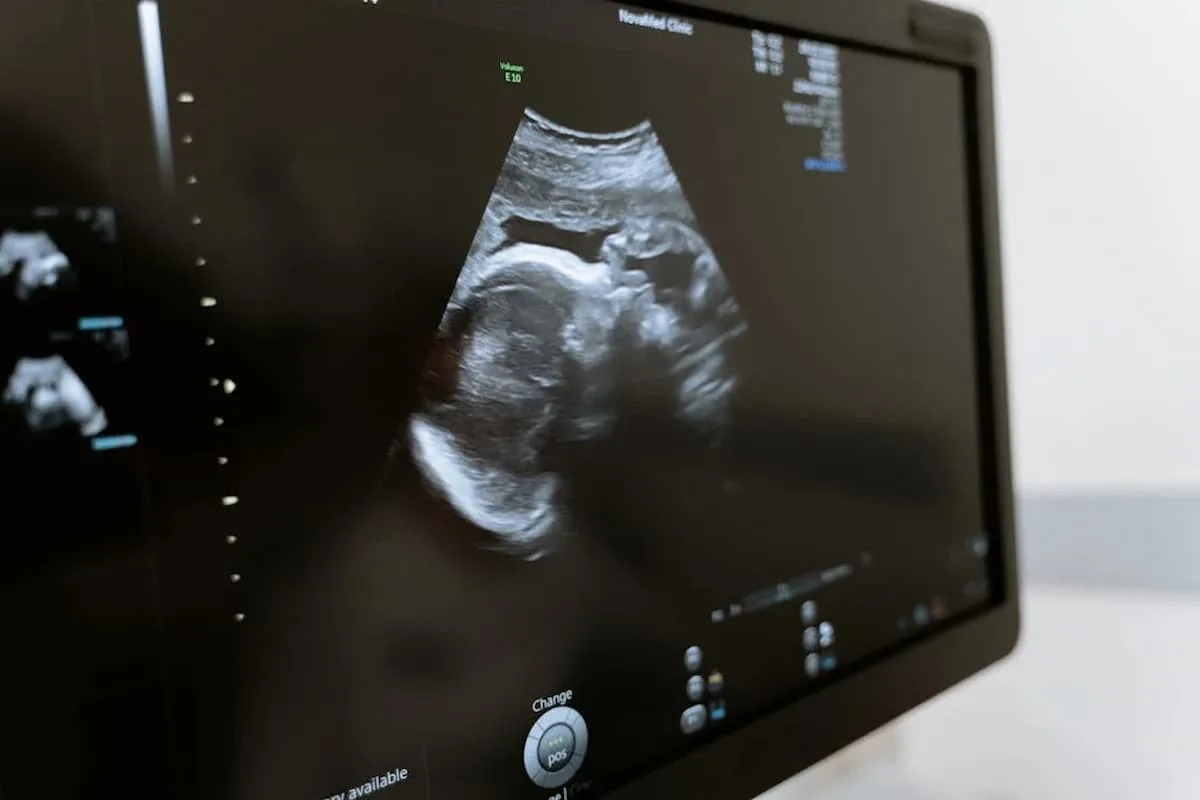

La profesional de Clínica de la Mujer es enfática en señalar que “el aborto precoz puede condicionar la complicación del duelo ya que, al ser una pérdida no visible, dado que ese bebé formaba parte del cuerpo de la mujer, de alguna manera, es un dolor que se tiende a minimizar, y los estudios hablan que independiente de que se trate de un aborto precoz o tardío, la duración del proceso de duelo, puede ser igual de intenso en ambos casos”.